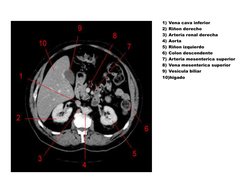

1) Vena cava inferior

2) Rion derecho

3) Arteria renal derecha

4) Aorta

5) Rion izquierdo

6) Colon descendente

7) Arteria mesenterica superior

8) Vena mesenterica superior

9) Vesicula biliar

10)higado